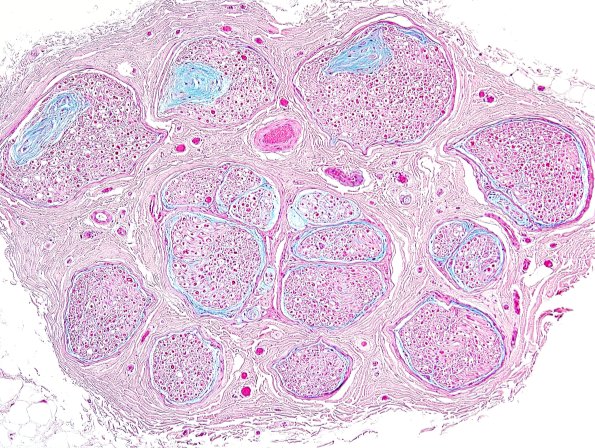

10B1-3 The RB are rich in Alcian Blue. Notice the subperineurial staining as well. (Alcian Blue)